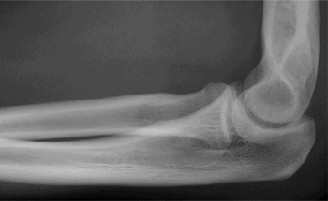

It should be noted that reverse total shoulder arthroplasty is also the procedure of choice in patients with cuff-tear arthropathy (aka rotator cuff arthropathy). Characteristics of cuff-tear arthropathy include superior migration of the humerus due to a massive rotator cuff tear, glenohumeral joint destruction, subchondral osteoporosis, and humeral head collapse (see Fig. 2–17). A reverse total shoulder

Figure 2–17_X-rays of a patient showing evidence of cuff tear arthropathy. The humerus is migrated superiorly, the glenohumeral joint is destroyed, there is subchondral osteoporosis, and the humeral head is collapsed. (From Ecklund KJ, Lee TQ, Tibone J, Gupta R. Rotator cuff tear arthropathy. _J Am Acad Orthop Surg. 2007;15(6):340–349.)